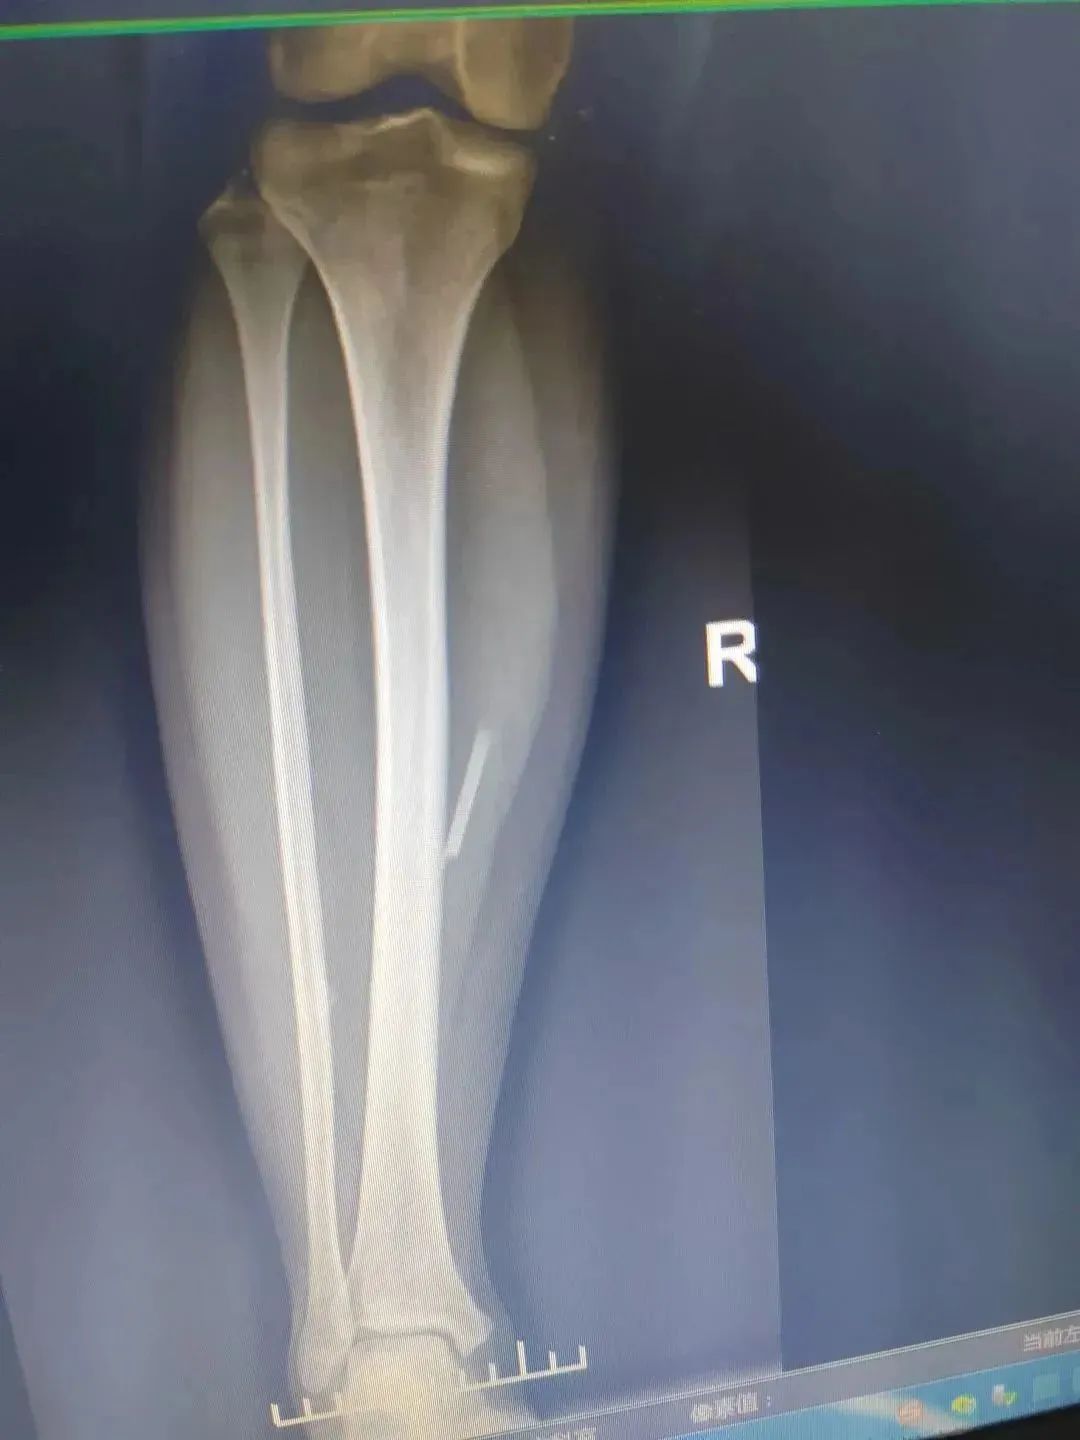

8月23日,两台肾移植手术在南宁顺利完成。器官的捐献者是一位来自广西河池的30多岁的水族青年。8月19日,小韦(化名)因脑出血在当地的医院救治,...

37岁的河池水族小伙小韦(化名)走了但他把“生命的礼物”留在了这个世界挽救3名器官衰竭患者的生命并让2名眼疾患者重见光明930老友记,赞98月20...

今天(8月23日)凌晨4时,在简短的告别仪式后,30多岁的河池水族小伙子小韦(化名)完成了人生的最后一次“助人”,将自己的肝脏、两个肾脏和一对眼角...

8月23日,两台肾脏移植手术在南宁进行,捐献者是一位来自河池的青年。他捐献了肝脏一枚、肾脏两枚、眼角膜一对,将挽救3名器官衰竭患者的生命,并...